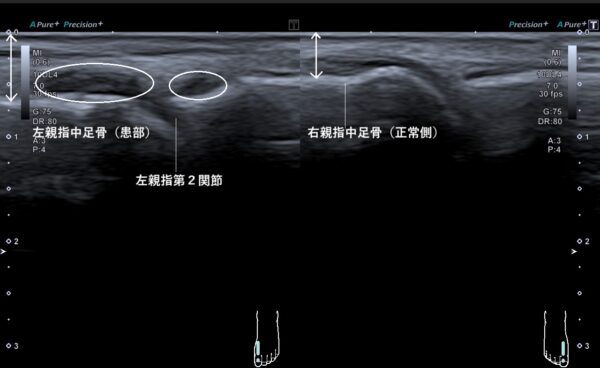

それらの所見から、第2関節を超音波(エコー)画像観察してみると関節の中に水(関節液)が過剰に溜まっていました(画像、白丸の中の黒い箇所)。

さらに、関節液が過剰に溜まっていることで腫れていることも視覚的に確認できます(画像、両矢印の長さの比較)。ですが、ひびは入っていませんでした。